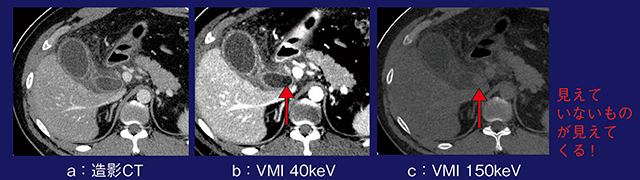

症例7は,38歳,男性,胆囊炎疑いである。造影CT(図7 a)では胆囊の腫大と壁の肥厚が認められるが,胆石は見られないため無石性胆囊炎と考えられた。しかし,仮想単色X線画像の40keV画像(図7 b)および150keV画像(図7 c)で微細な胆囊結石が認められた。最近の論文では,仮想単色X線画像によって従来の120kVで撮影した画像では見えていない胆石が描出されることが報告されている。単色X線エネルギーの変化に伴う胆汁と胆石のCT値の変化を見ると,40keVでは胆石は−50HU,胆汁は20HUであるのに対し,通常のCT画像(120kVp)に相当する70keVではいずれも10HU程度と,最も画像化されづらい値となっていた。さらに高エネルギーになると胆石のCT値が上昇し,胆汁とのCT値差によって胆石の描出能が向上する。

図7 症例7:仮想単色X線画像による胆囊結石の検出